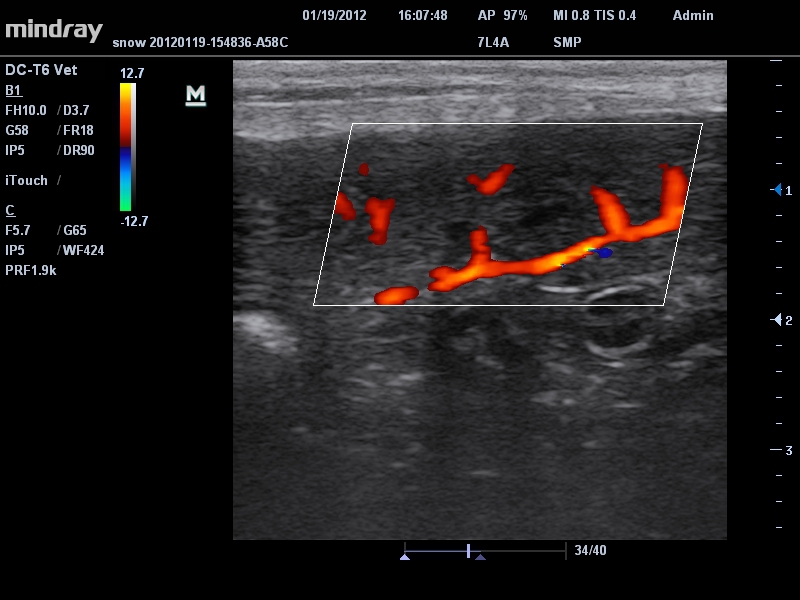

Mindray DC-T6

Ультразвуковая система Mindray DC-T6 – это инновационный аппарат для проведения высокого уровня диагностики с качественной визуализацией и широким спектром применения. Платформа рекомендована для использования в коммерчески многопрофильных медицинских учреждениях и государственных лечебных клиниках.

• Линейный ультразвуковой датчик Mindray 7L4A